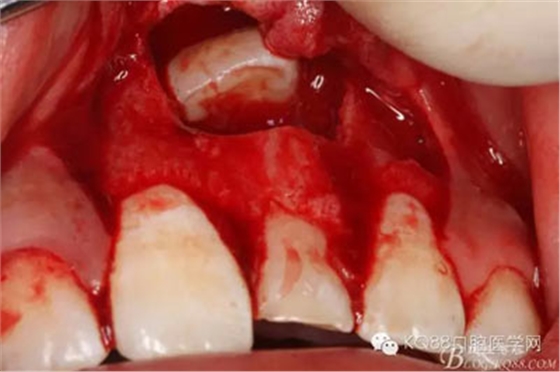

圖13.超聲骨刀清理周圍組織,21有Ⅰ°松動

圖14.牙冠周圍滲血多,無法粘結(jié)托槽。位置也高,隨與家屬溝通,暫時保留乳Ⅰ。待21初步穩(wěn)定,再考慮正畸牽引

圖15.輕輕的把21牙冠牽引至乳Ⅰ根尖方向,并擺正牙冠位置。(拔苗助長)